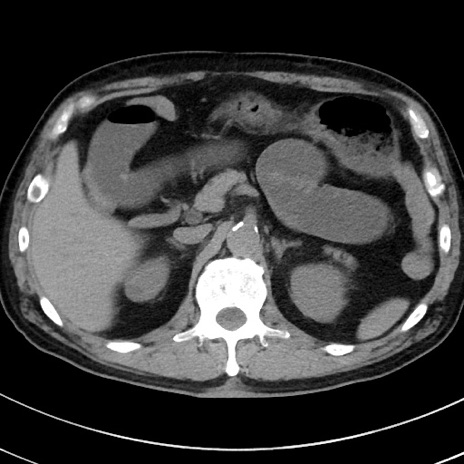

症例38(横断像)

【症例】70歳代 男性

【主訴】腹痛・嘔吐

【現病歴】昨晩より、嘔吐・腹痛あり。今朝になっても嘔吐あり。来院。

【既往歴】心臓バイパス手術、開腹胆摘、腸閉塞

【身体所見】BP 107/71mmHg、HR 116/min、腹部:平坦、軟、下腹部に軽度圧痛あり。反跳痛なし。

【データ】WBC 15100、CRP 0.32